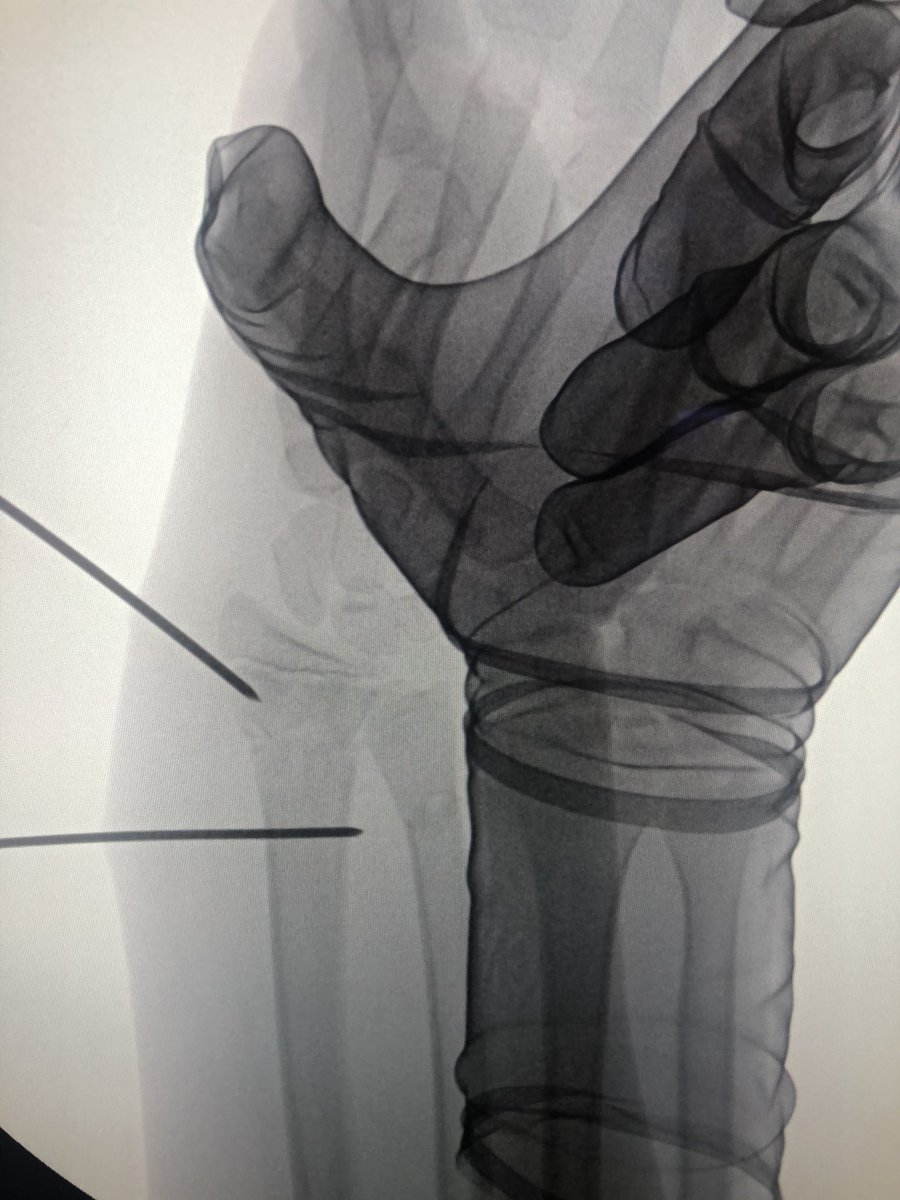

[1/4] Older child with distal both bone forearm with significant coronal plane translation. I thought this would continue to drift radially with time and would not end up looking good in a cast.

[2/4] This is the best closed reduction I could get and I didn’t want the morbidity of opening it to get it better. So I lined up the wire distal to the physis, and another one further proximally. The distal wire is smooth, but the proximal is threaded.... why?...